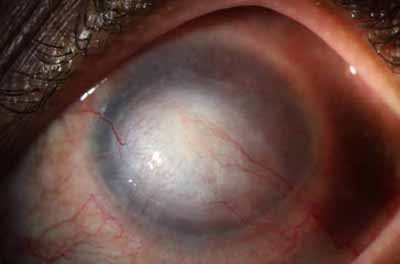

En su evolución se observará aumento del edema, aparición de un anillo inmunológico (Wessely), agrandamiento y coalescencia de los infiltrados que progresan hacia la formación de un absceso, queratolisis superficial, adelgazamiento y perforación corneal.

La vascularización y el hipopion son poco frecuentes en los estadios tempranos de la queratitis. Con el tiempo, en los estados avanzados de invasión estromal, aparecen vasos estromales

Início síntomas 60 dias - No PL

PAS

primer dia

1 mes

3 mes

5 mes